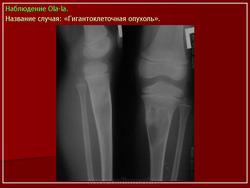

Гигантоклеточная опухоль.